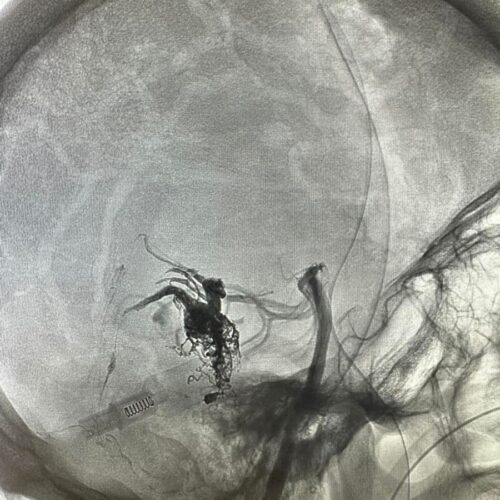

Δια ζώσης συμμετοχή των φοιτητών του Πανεπιστημίου Πατρών σε εξειδικευμένες τεχνικές ενδοαγγειακής αντιμετώπισης αγγειακών δυσπλασιών του κεντρικού νευρικού συστήματος.

Στην επέμβαση συμμετείχαν ο Καθηγητής Ενδοαγγειακής Νευροχειρουργικής Κος Β. Παναγιωτόπουλος, ο Καθηγητής Επεμβατικής Νευροακτινολογίας κος Π. Ζαμπάκης, ο επιμελητής επεμβατικής ακτινολογίας κος Μ. Θεοφάνης και ο αναισθησιολόγος κ. Γούδας.